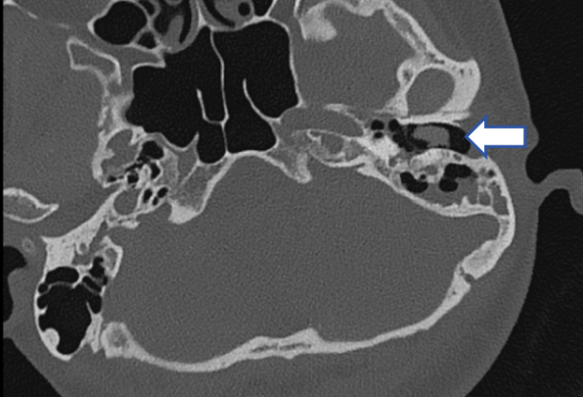

45岁的李女士,间断右侧搏动性耳鸣已经好几年,尤其在打哈欠时容易出现,轰轰声,与脉搏同步,耳朵里像装上了小马达。查看双侧外耳道、鼓膜都没有异常,进一步做了CT检查,发现:

CT示:右乙状窦憩室侵入右颞骨及乳突气房

初步诊断

血管性耳鸣、乙状窦憩室